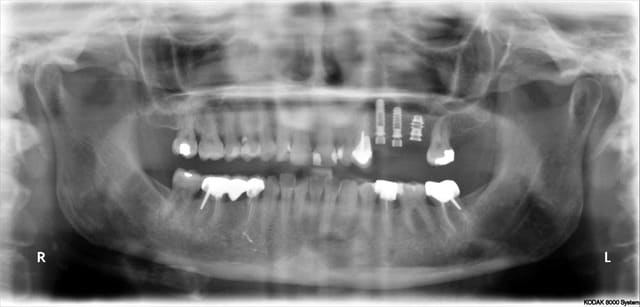

aujourd'hui

photo2 cas de droite

Dans d'autres posts certains critiques les implants léones. Sans commentaires sur les choix de chacun, mais les planifications continueront à être faites avec car ce sont ceux que j'utilise